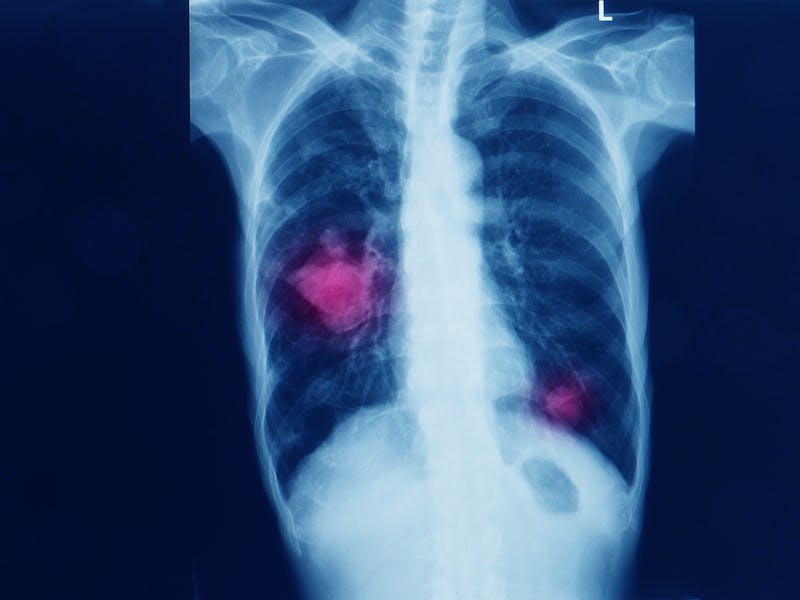

Researchers at the University of Waterloo in Canada have developed an A.I. system that can accurately diagnose 32 different forms of cancer 100 percent of the time. It was created using 30,000 digital images of tissue samples, and it compares images of biopsies where there was a positive cancer diagnosis with a new image from someone who hasn't yet been diagnosed to make its determination. The research was published earlier this month in the journal Nature Digital Medicine.

The A.I. system can diagnose melanoma, prostate cancer and many other types of cancer. The images that were used to create it were provided by the National Cancer Institute in the United States. Tizhoosh said having access to such a large archive made this possible.